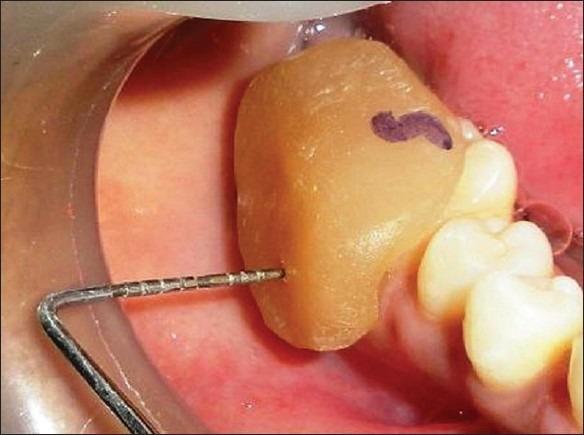

The present study was undertaken to evaluate the effectiveness of the combination of hydroxyapatite and β-tricalcium phosphate bone alloplast with bioresorbable guided tissue regeneration membrane for the treatment of mandibular grade II furcation defects.

A total of eight patients, four females and four males, in the age group of 18 to 65 years, with bilateral buccal grade II furcation defects in the mandibular molars, participated in the study.

The mean gain in the relative clinical attachment levels in the test and control groups, at the end of six months, were 2.50 and 1.63 mm, respectively. The mean change in the horizontal probing depth values at the end of six months in the test and control groups were 2.88 and 1.63 mm, respectively. The mean reduction in the vertical probing depth values in the test and control groups were 1.50 and 1.38 mm, respectively.

The resorbable GTR membrane with bone material was more effective than open debridement alone, in the treatment of furcation defects.